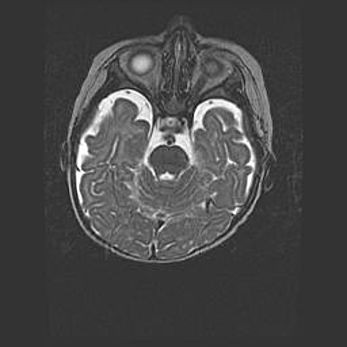

Ниже представлена  галерея МРТ снимков, полученных с применением LMT неонатальных матричных РЧ катушек. Также каждая группа МРТ снимков сопровождается информацией о пациенте (диагноз, возраст, вес, пол, срок гестации) и краткой сопроводительной расшифровкой диагноза.

Множественные кисты обоих полушарий головного мозга, наибольшая из них в правой затылочной области. Ассиметричная атрофическая гидроцефалия.

Возраст: 7 месяцев

Вес: 5660 г

Пол: мужской

Окружность головы: 41,5 см

Срок гестации: 28-29 недель

Кисты головного мозга развиваются в результате многоочаговых некрозов вещества мозга и возникают вследствие перенесенной перинатальной инфекции, менингитов, энцефалитов, асфиксии, родовой травмы, расстройств мозгового кровообращения различного генеза. Образованию кист в веществе головного мозга плодов и новорожденных способствуют такие факторы, как высокое содержание в нем воды, недостаточная (или отсутствие) миелинизация и слабая астроглиальная реакция на повреждение.

Кисты могут сочетаться с гидроцефалией и другими поражениями головного мозга.